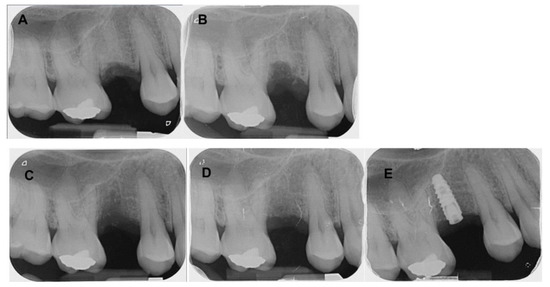

4.1. Patient No. 1

4.2. Patient No. 2

4.3. Patient No. 3

4.4. Patient No.4

4.5. Patient No.5

4.6. Patient No.6